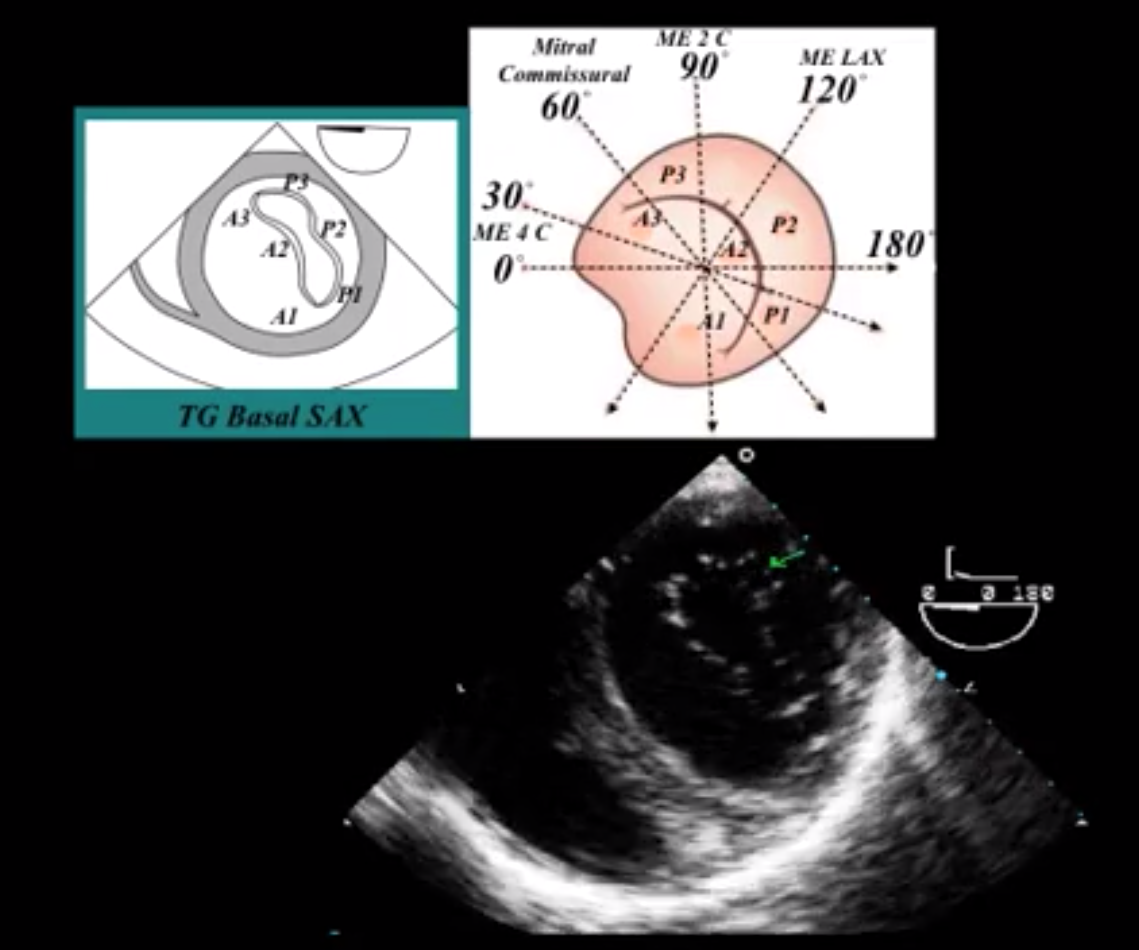

What view is seen here?

Basal Short Axis View

What view of the Mitral Valve is seen in the mid esophageal at approximately 0 - 30 degrees?

ME 4 chamber

What view of the Mitral Valve is seen in the mid esophageal at approximately 60 degrees?

ME Commissural View

What scallops are seen in the commissural view of the mitral valve?

P1 = Right

A2 = Center

P3 = Left

What view of the Mitral Valve is seen in the mid esophageal at approximately 90 Degrees?

Mid Esophageal 2 chamber

What view of the Mitral Valve is seen in the mid esophageal at approximately 120 degrees?

Mid Esophageal Long Axis